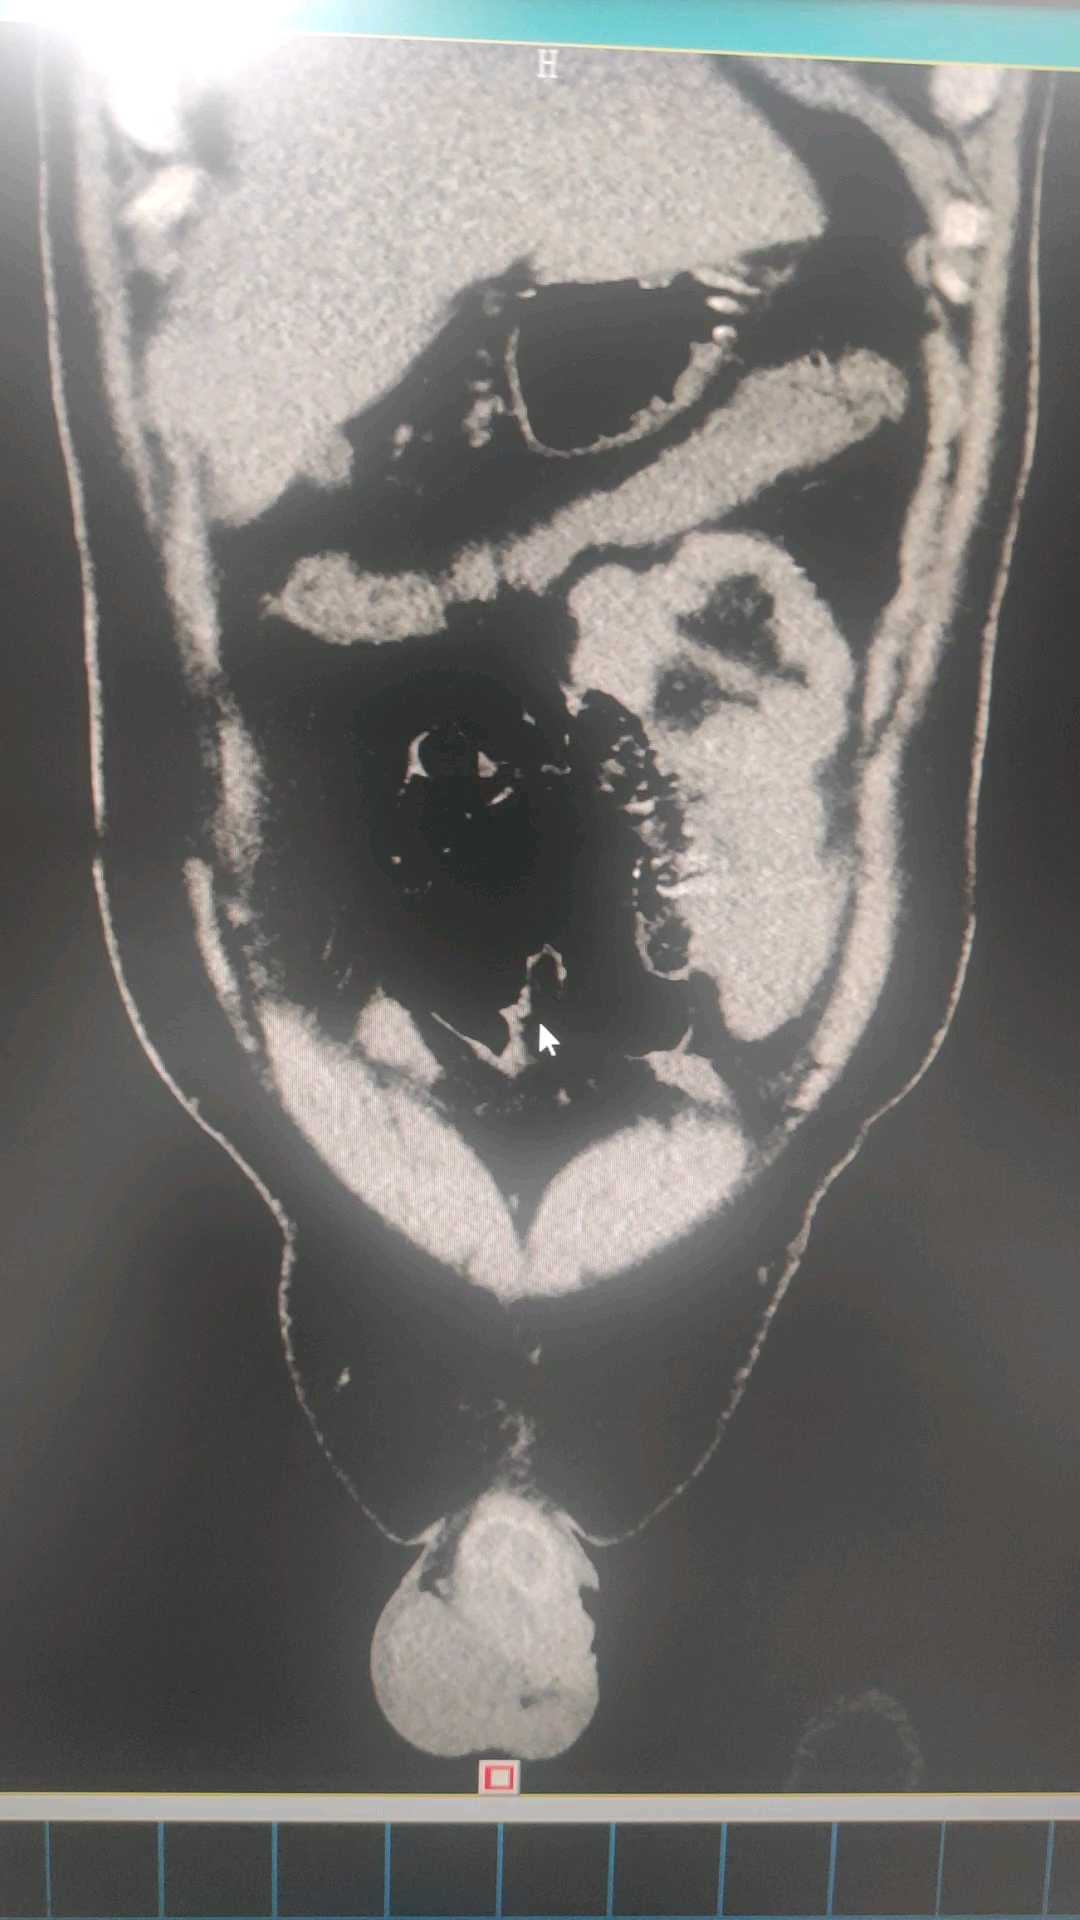

男性,37岁,因“右下腹闷痛2天”于2025-10-25入院,右下腹压痛,反跳痛明显